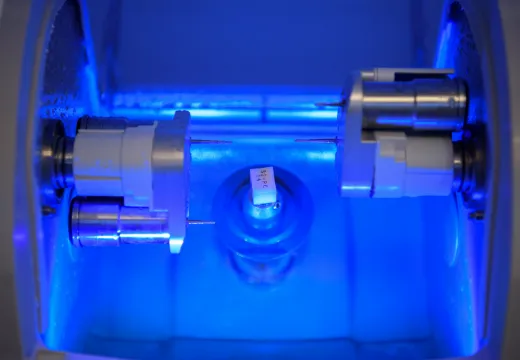

MEDICAL EQUIPMENT

CTスキャンを活用し、

患者様の口腔内を3Dモデル化

えみは総合歯科のインプラント治療は、CTスキャンで口腔内の3Dモデルを作成し、コンピュータシステム「ビオナ」を使用して歯の状態を正確に解析・診断します。

専門医とコンピュータから、精密なインプラント挿入の治療計画を作成します。機械技術と医師の腕が合わさり、患者様の手術への不安や負担を軽くして、手術(インプラント埋め込みの位置・角度)の誤差も従来のものと比べて格段に下がり、ミリ単位の誤差に抑える安全正確な手術になっています。

セレックで

人工歯を正確に製造し、

治療スピードが向上!

当院が使用するセレックは、天然歯に近い色と質感のセラミックを使用して、高精度3Dコンピューターで詰め物や被せものを設計・加工します。

金属を使用しないので、金属アレルギーなども心配もありません。

インプラントのかぶせものとして、他の歯とのかみ合わせにも優しく、通院・麻酔の回数も通常よりも少なく身体に安全安心です。